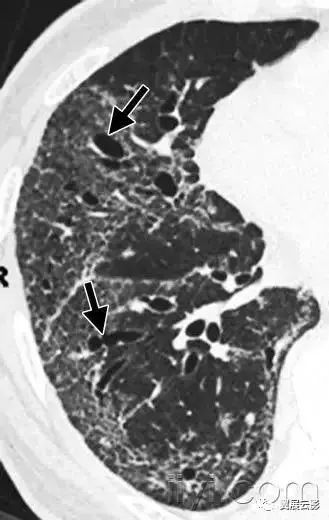

十八、小叶中心性:

解剖:小叶中心性用于描述次级肺小叶的支气管血管束中心区域。病理学上也用这一术语描述终末小支气管远端,位于呼吸性细支气管和肺泡管中心的病变。

CT:正常次级肺小叶中心的点状或者线状的密度增高影,胸膜下25px范围内最明显,代表小叶内的动脉,直径约1mm。

小叶中心性异常包括(1)结节(2)树芽征,提示小气道病变(3)由于临近间质的增厚或者浸润导致小叶中心结果更加清晰(4)小叶中心性肺气肿导致的异常低密度。

附图为小叶中心性肺气肿